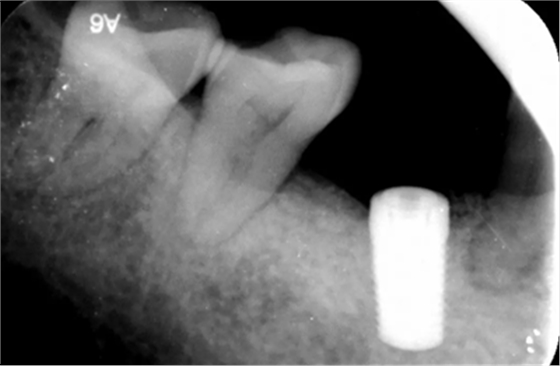

15、植骨术后半年再次二期手术过程

植骨术后半年根尖片,种植体周围愈合较好远中少量骨吸收。

(摄于2018年4月20日)